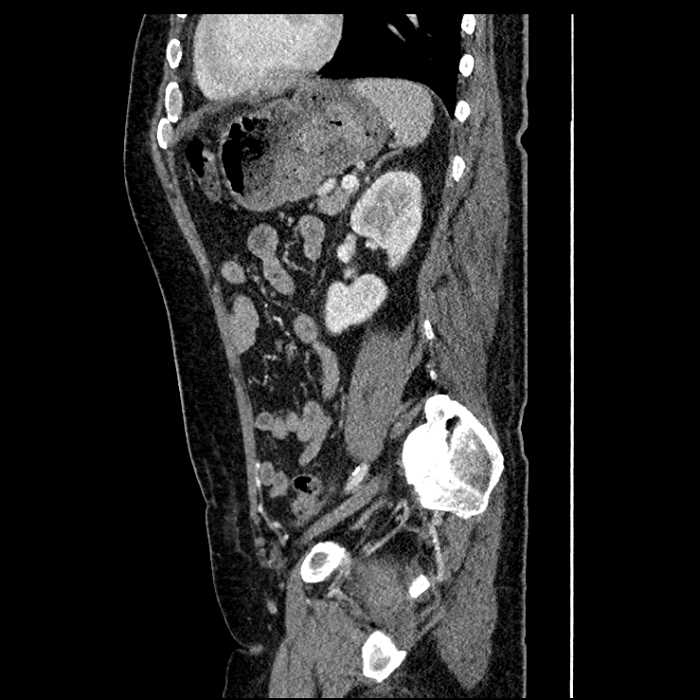

Age: 63

Sex: Male

Indication: Abdominal pain

• Large fluid density structure in hepatic segments 7 and 8 measuring 10 x 7 x 7 cm with internal septation and circumferential ill-defined low density compatible with edema

• Peripherally enhancing subcapsular collections along the anterior margin of the left hepatic lobe measuring 3 x 1 cm and 2 x 1 cm

• Clearly marginated fluid density structure in segment 7 and several other scattered tiny hypodensities, which likely represent cysts

• Hepatic abscess

Acute sigmoid diverticulitis complicated by a small contained perforation and a large abscess in the right hepatic lobe. Additional small subcapsular abscesses along the anterior margin of the left hepatic lobe.

Additionally, loss of the normal fat plane between the peridiverticular collection and adjacent thickened loops of small bowel raises the potential for an enterocolonic fistula.

• The classic CT imaging appearance is a double target sign with internal low density surrounded by an internal enhancing rim (capsule) and a low density external rim (edema)

• Abscesses may be unilocular or multilocular

• Gas is present in a minority of cases

Hepatic abscess showing the double target sign with low density internally surrounded by a thin inner enhancing rim (red arrow) and ill-defined outer low density rim (yellow arrow). Blue arrow indicates an internal septation. Red arrows: additional smaller subcapsular abscesses. Red arrow: focal contained perforation associated with diverticulitis.